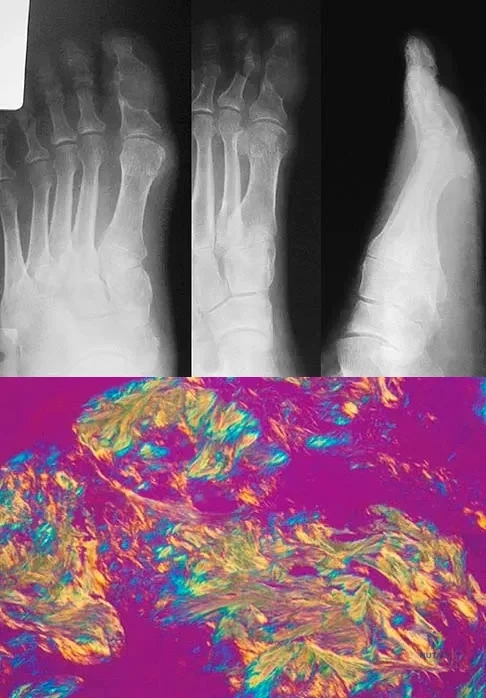

Question 13

An 83-year-old man has a painful mass of the great toe. Radiographs and a biopsy specimen are seen in Figures 22a and 22b. What is the most likely diagnosis?

Explanation